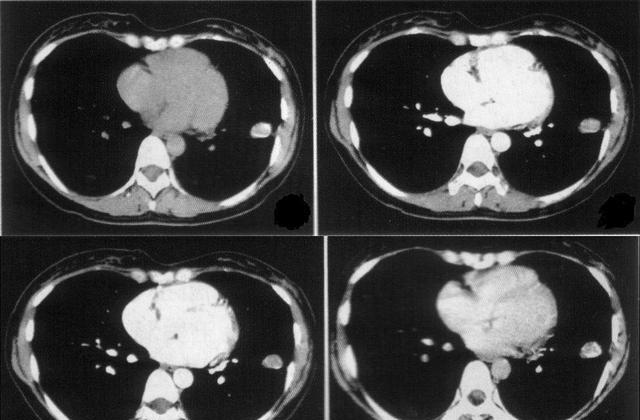

年龄越来越大,藏大叔的肺也逐渐出现 问题 ,刚开始还不在意,直到忍不了才和儿子说,在儿子的坚持下去看了医生,做了全身体检。没想到这一体检还真出毛病了,竟然患了肺结核,肺也有轻微的 炎症 。

医生说,幸好发现得早,否则后果不堪设想,很有可能会 危及生命 。